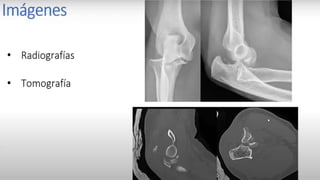

Tratamiento de la luxación del codo

Reducción bajo sedaciónoanestesiageneral :

Tracción del antebrazo

en flexión de codo

contra tracción del brazo

± presiónsobre el olécranon

Yeso braquipalmar en f lexióndurante 3 semanas

Reduction of a posterior elbow dislocation consists of longitudinal traction (A),

correction of lateral or medial displacement (B), and flexion of the elbow (C).